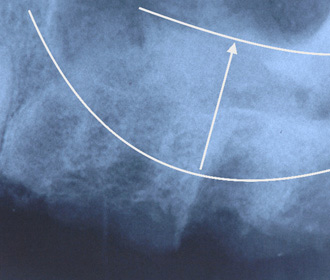

インプラント治療直後のレントゲン写真。

網目状のものがチタンメッシュ、ピンで骨に固定。 -